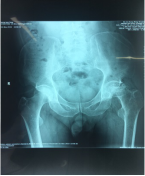

11月份门诊诊疗病例80余人次,病种大多为颈椎病、腰椎间盘突出症、腰椎管狭窄症、梨状肌紧张综合征、胸腰椎小关节紊乱症、小儿髋关节滑膜崁顿、膝关节骨性关节炎、膝关节滑膜炎、肩关节周围炎、股骨头坏死、距骨坏死及桡骨远端骨折、锁骨骨折、尺骨鹰嘴骨折、尺骨骨折、股骨颈骨折、股骨大粗隆撕脱骨折、踝关节骨折、掌骨骨折、指骨骨折、跖骨骨折、趾骨骨折、肩关节脱位等。

手法整复桡骨远端骨折、踝关节骨折、尺骨骨折、掌骨骨折、指骨骨折、跖骨骨折及肩关节脱位、桡骨小头半脱位等各类骨折脱位十余例,行小夹板固定及石膏托外固定十余例。